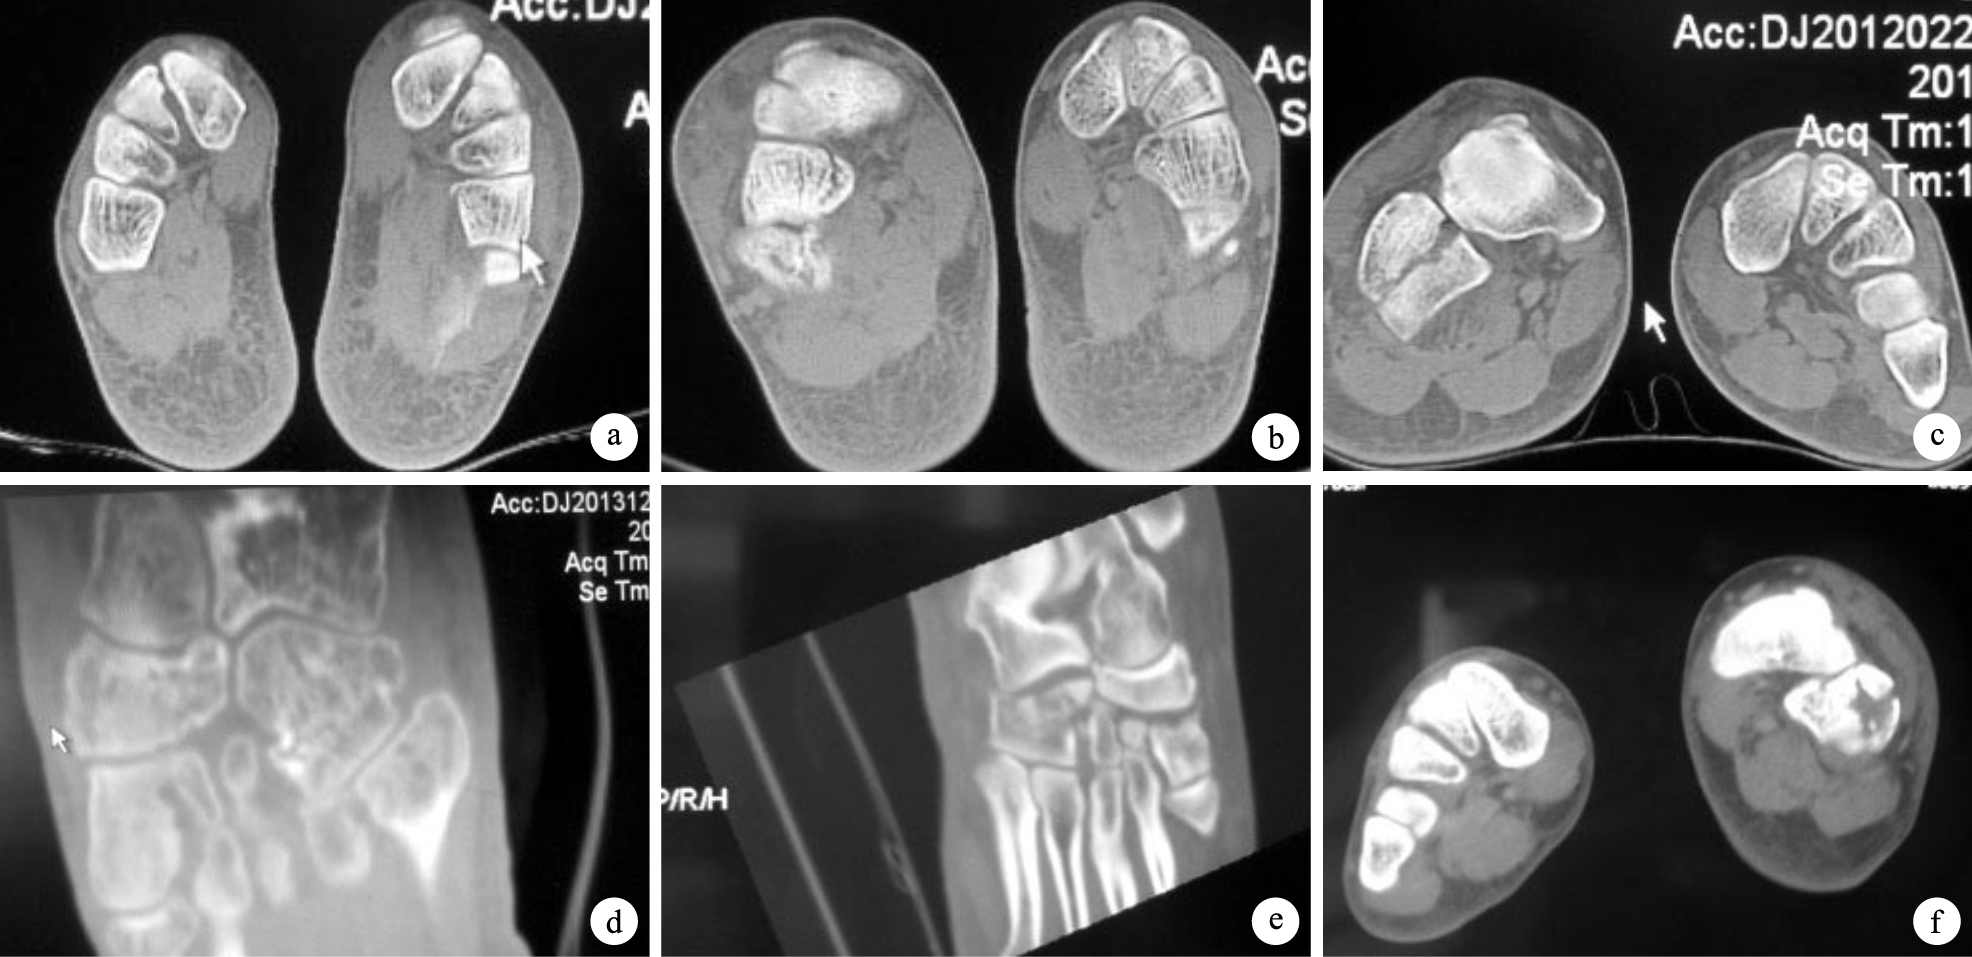

骰骨骨折改良分型標準:Ⅰ型,為骰骨不同部位的小顆粒樣或小薄片樣撕脫骨折,可累及關節邊緣。Ⅱ型,骨折線于不同方向通過或不通過關節面的無明顯骨質壓縮的塊狀骨折,包括2個亞型,其中Ⅱa型為骨折端間隙或關節面臺階≤1 mm;Ⅱb型為骨折端間隙或關節面臺階>1 mm。Ⅲ型,骨折線通過或不通過關節面并造成足外側柱短縮的壓縮骨折,包括3個亞型,其中Ⅲa型為骨折線不通過跗跖關節側及跟骰關節側關節面的體部壓縮骨折;Ⅲb型為骨折線通過跗跖關節側和/或跟骰關節側關節面,且單側關節側骨質壓縮的骨折;Ⅲc型為骨折線通過跗跖關節側及跟骰關節側的兩側關節面,且兩側骨質均壓縮的骨折。見圖 1。本組Ⅰ型285足(68.5%);Ⅱ型59足(14.2%),其中Ⅱa型18足(4.3%),Ⅱb型41足(9.9%);Ⅲ型72足(17.3%),其中Ⅲa型6 足(1.4%),Ⅲb型40足(9.6%),Ⅲc型26足(6.3%)。